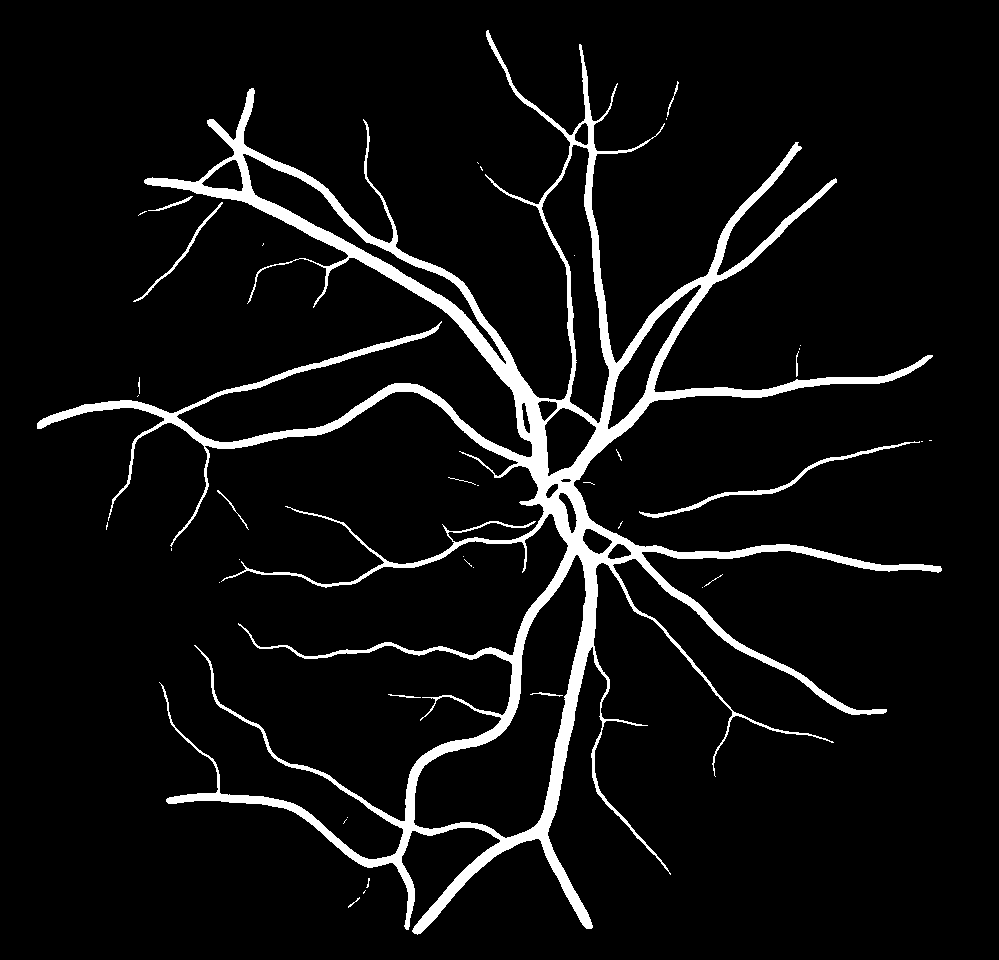

VI-B Vessel Width Estimation

Table VI presents a quantitative comparison of the measured diameters using the segmentation outputs of SegRAVIR and competing approaches. Using the pixel-wise annotated masks, the reference average diameter of the arteries and veins in the test set of the RAVIR dataset were measured as and , respectively. According to our analysis, SegRAVIR can accurately measure the diameter of the vessels and it achieves the smallest MAPE among the competing approaches. Specifically, in comparison to CE-Net, Iter-Net, and DU-Net, respectively, SegRAVIR is on average , and more accurate in terms of MAPE for the measured diameter of arteries and , and in terms of MAPE for the measured diameter of veins. Fig. 6 presents qualitative comparisons of reference and SegRAVIR estimated diameter maps.